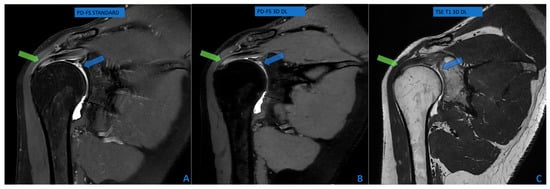

Biomechanical Comparison of Three Fixation Constructs for Tile Type C1.2 Pelvic Ring Fractures: A Finite Element Analysis

by Adrian Claudiu Carp, Bogdan Veliceasa, Dmour Awad, Alexandru Filip, Mihaela Perțea, Norin Forna, Bogdan Puha, Ștefan Dragoș Tîrnovanu, Mihnea Theodor Sîrbu, Silviu Dumitru Pavăl and Paul Dan Sîrbu

Life 2026, 16(2), 336; https://doi.org/10.3390/life16020336 - 15 Feb 2026

Fractures of the pelvic ring are among the most severe injuries in orthopaedic practice and Tile type C lesions are characterized by complete disruption of the posterior arch with both vertical and rotational instability. The optimal construct for posterior ring fixation remains a matter of debate. The aim of this study was to compare, by means of finite element analysis, the biomechanical performance of three different methods of osteosynthesis for Tile type C1.2 pelvic ring fractures: a transiliac plate, one iliosacral screw and two anterior reconstruction plates on the sacroiliac joint. A three-dimensional model of an intact pelvis was reconstructed from computed tomography images of a healthy adult male. A Tile type C1.2 injury pattern was created virtually, and three fixation constructs were designed in Ansys SpaceClaim according to manufacturer specifications. All materials were assumed to be homogeneous, isotropic and linearly elastic. Vertical loads of 400 N and 800 N were applied to the sacral endplate to simulate partial and full weight bearing, while the acetabular regions were constrained to represent standing stance. In this study, mechanical stability was operationally defined as resistance to global displacement under applied vertical load, with lower displacement indicating higher construct stiffness. Construct stiffness, total deformation and von Mises stress were assessed for bone and implants. For both loading conditions, the iliosacral screw construct showed the lowest overall displacement and provided the greatest stiffness. The transiliac plate construct presented larger displacements, whereas the anterior reconstruction plate construct provided intermediate stability with higher stresses at the sacroiliac joint. Among the analyzed constructs, the iliosacral screw provided the greatest stiffness and lowest overall displacement, suggesting superior mechanical performance under vertical loading conditions. Full article

Show Figures

Figure 1